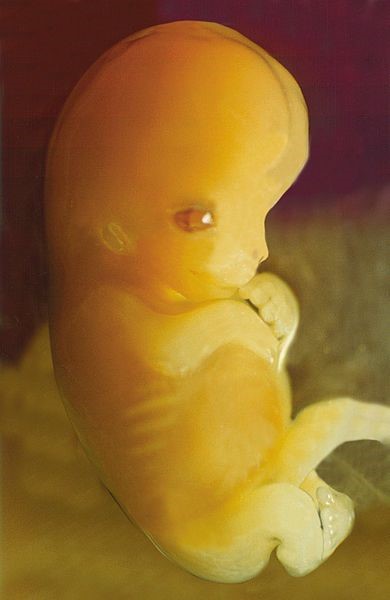

그런데 입덧도 쓴 맛을 느끼는 유전자와 비슷한 역할을 하는 것으로 보입니다. 진화생물학자 마지 프로펫(Margie Profet)에 의하면, 임신 초기 입덧은 해로운 물질이나 독소를 피하는 역할을 한다고 합니다. 임신 초기 3개월은 중요한 장기가 생겨나고, 뇌와 신경계가 발달하는 아주 중요한 시기입니다. 굳이 우선순위를 매기자면, 전체 9개월의 임신 기간 중에 첫 3개월이 제일 중요하다고 할 수 있습니다. 그래서 이 때는 태아에게 좋지 않은 음식, 특히 자극성 있는 음식이나 너무 익은 과일, 매운 음식, 훈제 음식 등에 대해서 구역감을 느끼게 되는 것입니다.

물론 구역감이 너무 심해서 음식을 제대로 먹지 못하면, 태아에게도 좋을 것이 없습니다. 하지만 첫 3개월 동안, 특히 입덧이 많이 일어나는 4-12주 사이에는 많은 영양분을 공급하는 것보다, 좋은 영양분을 공급하는 것이 더 중요합니다. 아직 태아는 아주 작아서 많은 영양소를 필요로 하지 않습니다. 하지만 조금이라도 나쁜 물질이 들어가면, 기형이 유발되기도 하고 심지어는 유산이 일어날 수도 있습니다. 위험한 시기가 지나면, 자연스럽게 입덧도 좋아집니다.

임신 첫 3개월은 대단히 위험한 시기입니다. 태아가 가장 취약한 시기인데도 불구하고, 상당수의 임산부는 자신이 임신한 사실도 잘 모르기 때문입니다. 이 시기에 영양분 결핍이 일어나면, 심각한 문제가 생길 수 있습니다. 리보플라빈(riboflavin) 부족은 골격발달에 문제를 유발하고, 비타민 B6 즉 피리독신(pyridoxine) 결핍은 신경운동계의 문제를 일으킵니다. 엽산이 부족하면 신경관 결함이 유발되고, 비타민 A가 부족하면 시각장애가 일어납니다. 앞서 말한 대로, 요오드(iodine)가 부족하면 신경 문제 및 크레틴병(cretinism), 즉 선천성 갑상선 기능 저하증을 유발합니다.

인간의 태반은 아주 독특합니다. 다른 포유류와 달리, 어머니의 자궁 속으로 아주 깊이 파고들 뿐 아니라 태반막도 아주 얇습니다. 큰 뇌에 필요한 엄청난 양의 산소와 영양분을 충분히 공급하기 위해서 그렇게 진화한 것입니다. 하지만 이렇게 깊게 유착된 얇은 태반막은 중대한 단점이 있습니다. 산소처럼 좋은 것만 쉽게 전달되는 것이 아니라, 독소나 유해물질도 쉽게 지나간다는 것입니다. 그래서 임신 초기에는 입덧이 아니더라도, 특히 조심조심 가려 먹어야 합니다.